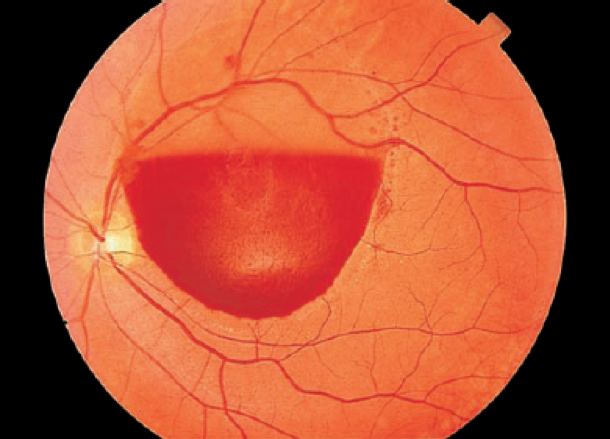

Heamorhage infront of the retina and obscuring vision( Subhyaloid vitreous haemorrhage)